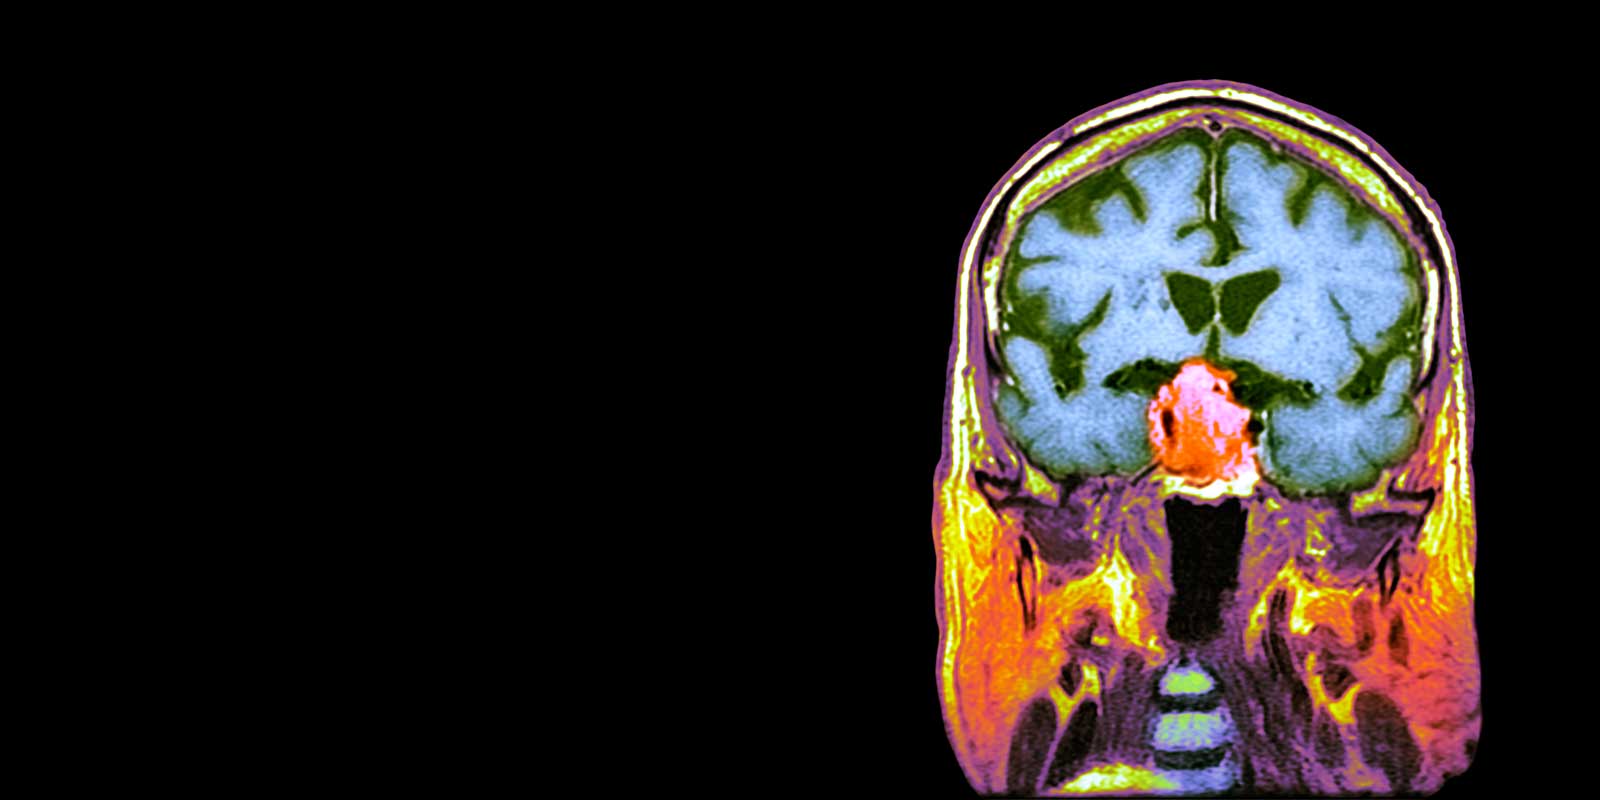

A pituitary tumor is a growth of abnormal cells in the pituitary gland, a pea-sized organ located at the base of the brain just behind the eyes. Sometimes referred to as the “master endocrine gland” because it produces hormones that affect the way many parts of the body work, the pituitary gland also controls hormones made by other glands in the body.

Nearly all pituitary tumors are benign (noncancerous) glandular tumors called pituitary adenomas. Nevertheless, benign pituitary tumors can cause serious health issue due to their location in the brain, their ability to spread to nearby tissues (i.e., the skull and the sinuses) and their tendency to produce excess hormones. Microadenomas are pituitary adenomas that are smaller than 1 centimeter, while those larger than 1 centimeter are called macroadenomas. The majority of pituitary adenomas are microadenomas.